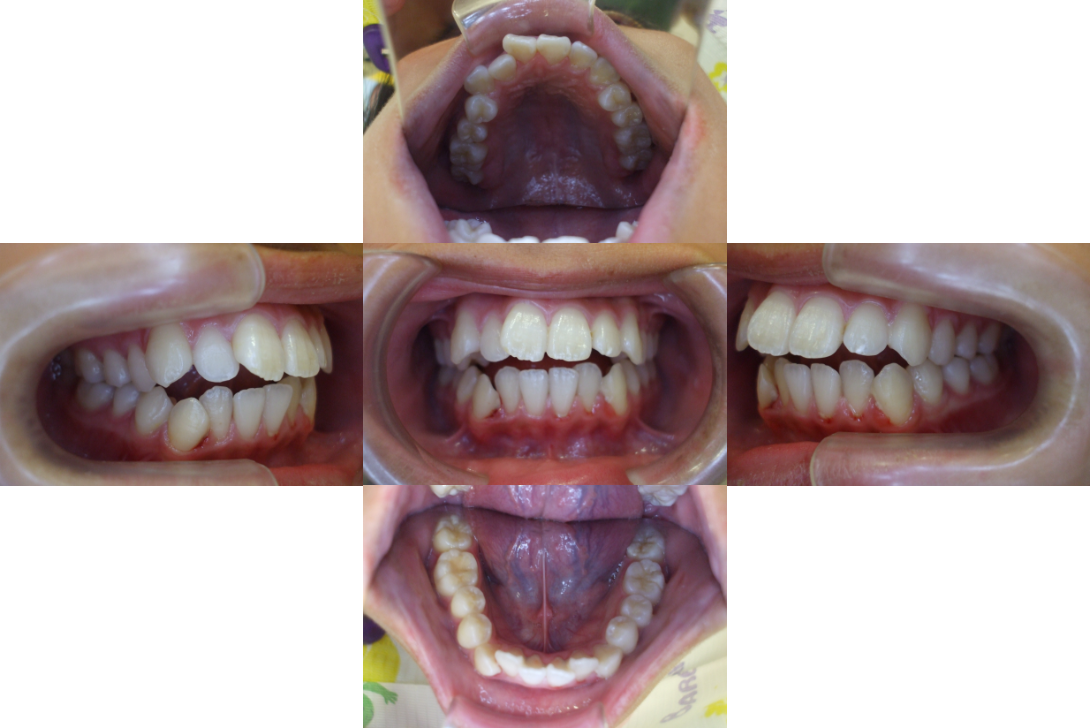

開咬(オープンバイト)を抜歯、インプラントアンカー、DBSで改善した症例

※DBSとはダイレクトボンディングシステムと呼ばれており、ブラケットにワイヤーを通して歯を動かしていく矯正治療です。

患者情報

16歳女性

主訴

前歯の隙間が気になる

行った治療内容

上顎両側4番抜歯、下顎左側1番抜歯 上顎インプラントアンカー、顎間ゴム、DBS

治療のリスク

歯根吸収、前歯部歯肉退縮

治療期間

3年6か月

※ クリックして拡大することができます。